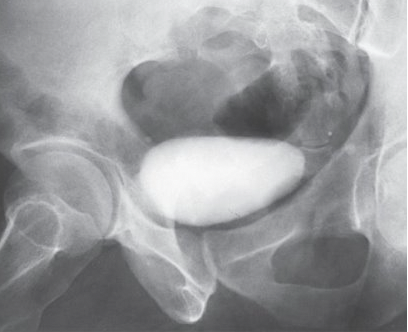

What is the patient position for an AP oblique for a male cystourethrography

35-40 degree posterior oblique

What is this projection and what is the CR angle?

AP axial with CR angled 10-15 degrees caudal